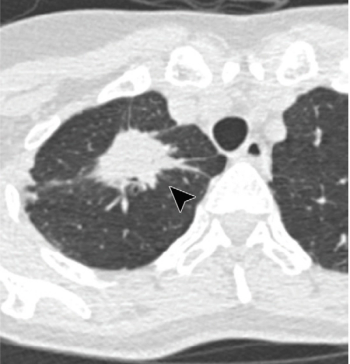

Using a structured reporting approach, radiologists are better able to predict which patients will also have a positive RT-PCR result.

A commercially available deep learning algorithm performed comparably to the individual radiologist when assessing patients at low risk for the disease.